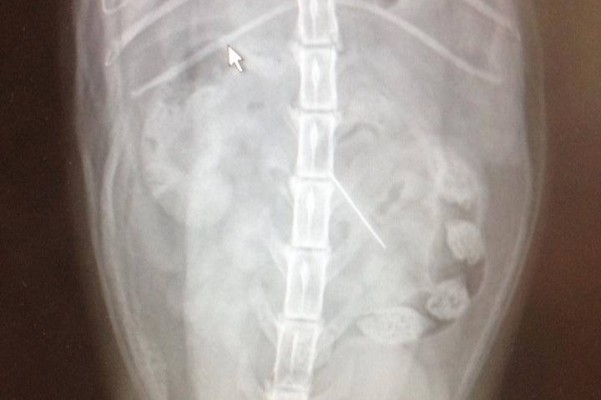

Prim is my cat and she is only two and a half years old. She swallowed a needle and thread, and she needs surgery immediately. I cannot afford a $3000 surgery by myself, and it would be a cruel reason to have to put her down because I can't afford her surgery. Please help me keep this furry member of my family. Please help me save her.